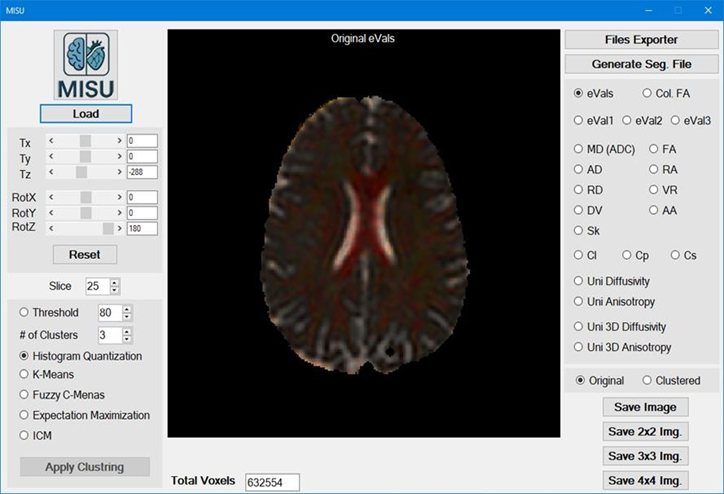

Loading the File: Image Clustering Utility is the main form (Figure 1) of the application. Just load MIS-U file or any Image files (BMP, PNG, JPG) and then you are ready to go.

Figure 1: Main Form of MIS-U application showing the original image view.

When loading MIS-U file: For DTI modality, all Scalar Indices (SI) + Unistable and Unistable 3D are included, however for other modalities (MRI, CT, Flair … etc.) only magnitude, Unistable and Unistable 3D would be available.

When Loading Image File: Only magnitude will be available.

Clustering Algorithms: According to the selected image, Clustering algorithm can be applied.

You can select simple threshold clustering or use one of the following clustering algorithms:

• Histogram Quantization

• K-Means

• Fuzzy C-Means (FCM)

• Expectation Maximization (EM)

• Iterated Conditional Mode (ICM)

Just specify the algorithm and the required number of clusters and click the button.